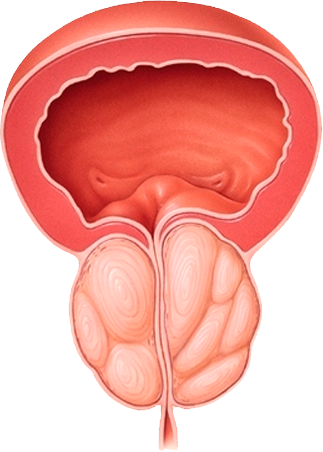

“La detección oportuna

de cáncer de prostata

salvó mi vida”

- Raúl Gómez Soriano